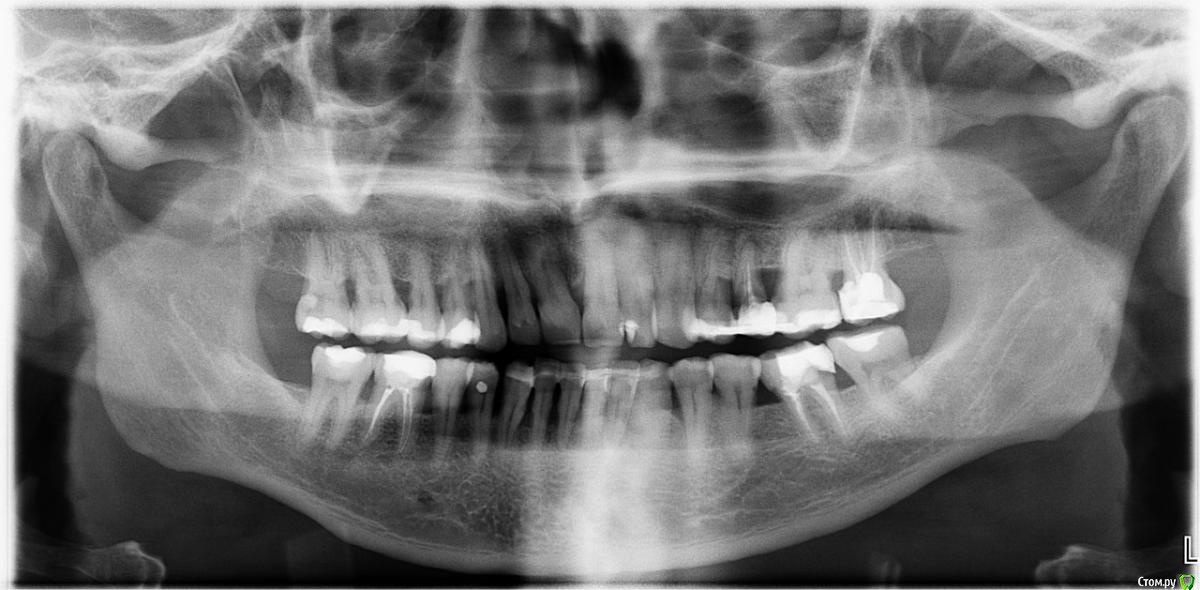

krokomot Опубликовано 11 сентября, 2019 Поделиться Опубликовано 11 сентября, 2019 Нужен рентген, до какого уровня скол, можно сепарировать десну провести препарированме сыормировать десневой контур на новом уровне, в области нижних зубов не рекомендую делать гингив эктомию, только перемещение. Ссылка на комментарий

DmitrySH Опубликовано 24 сентября, 2019 Поделиться Опубликовано 24 сентября, 2019 Не вижу никаких особых сложностей. убрать пломбу, оценить то что имеем в итоге. далее или билдап или вкладку. Временной коронкой сформировать контур десны. И объяснить пациенту необходимость лечения и ортопедического восстановления 25,27, 36, для избежания подобных случаев Ссылка на комментарий